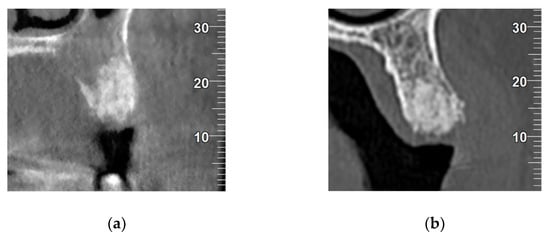

- Absent: When no union was observed between vestibular and palatine/lingual cortical at alveolar crestal level (Figure 3a).

- Partial: When the union between vestibular and palatine/lingual cortical was interrupted at alveolar crestal level (Figure 3b).

- Complete: When union was observed between vestibular and palatine/lingual cortical bone at alveolar crestal level (Figure 3c).